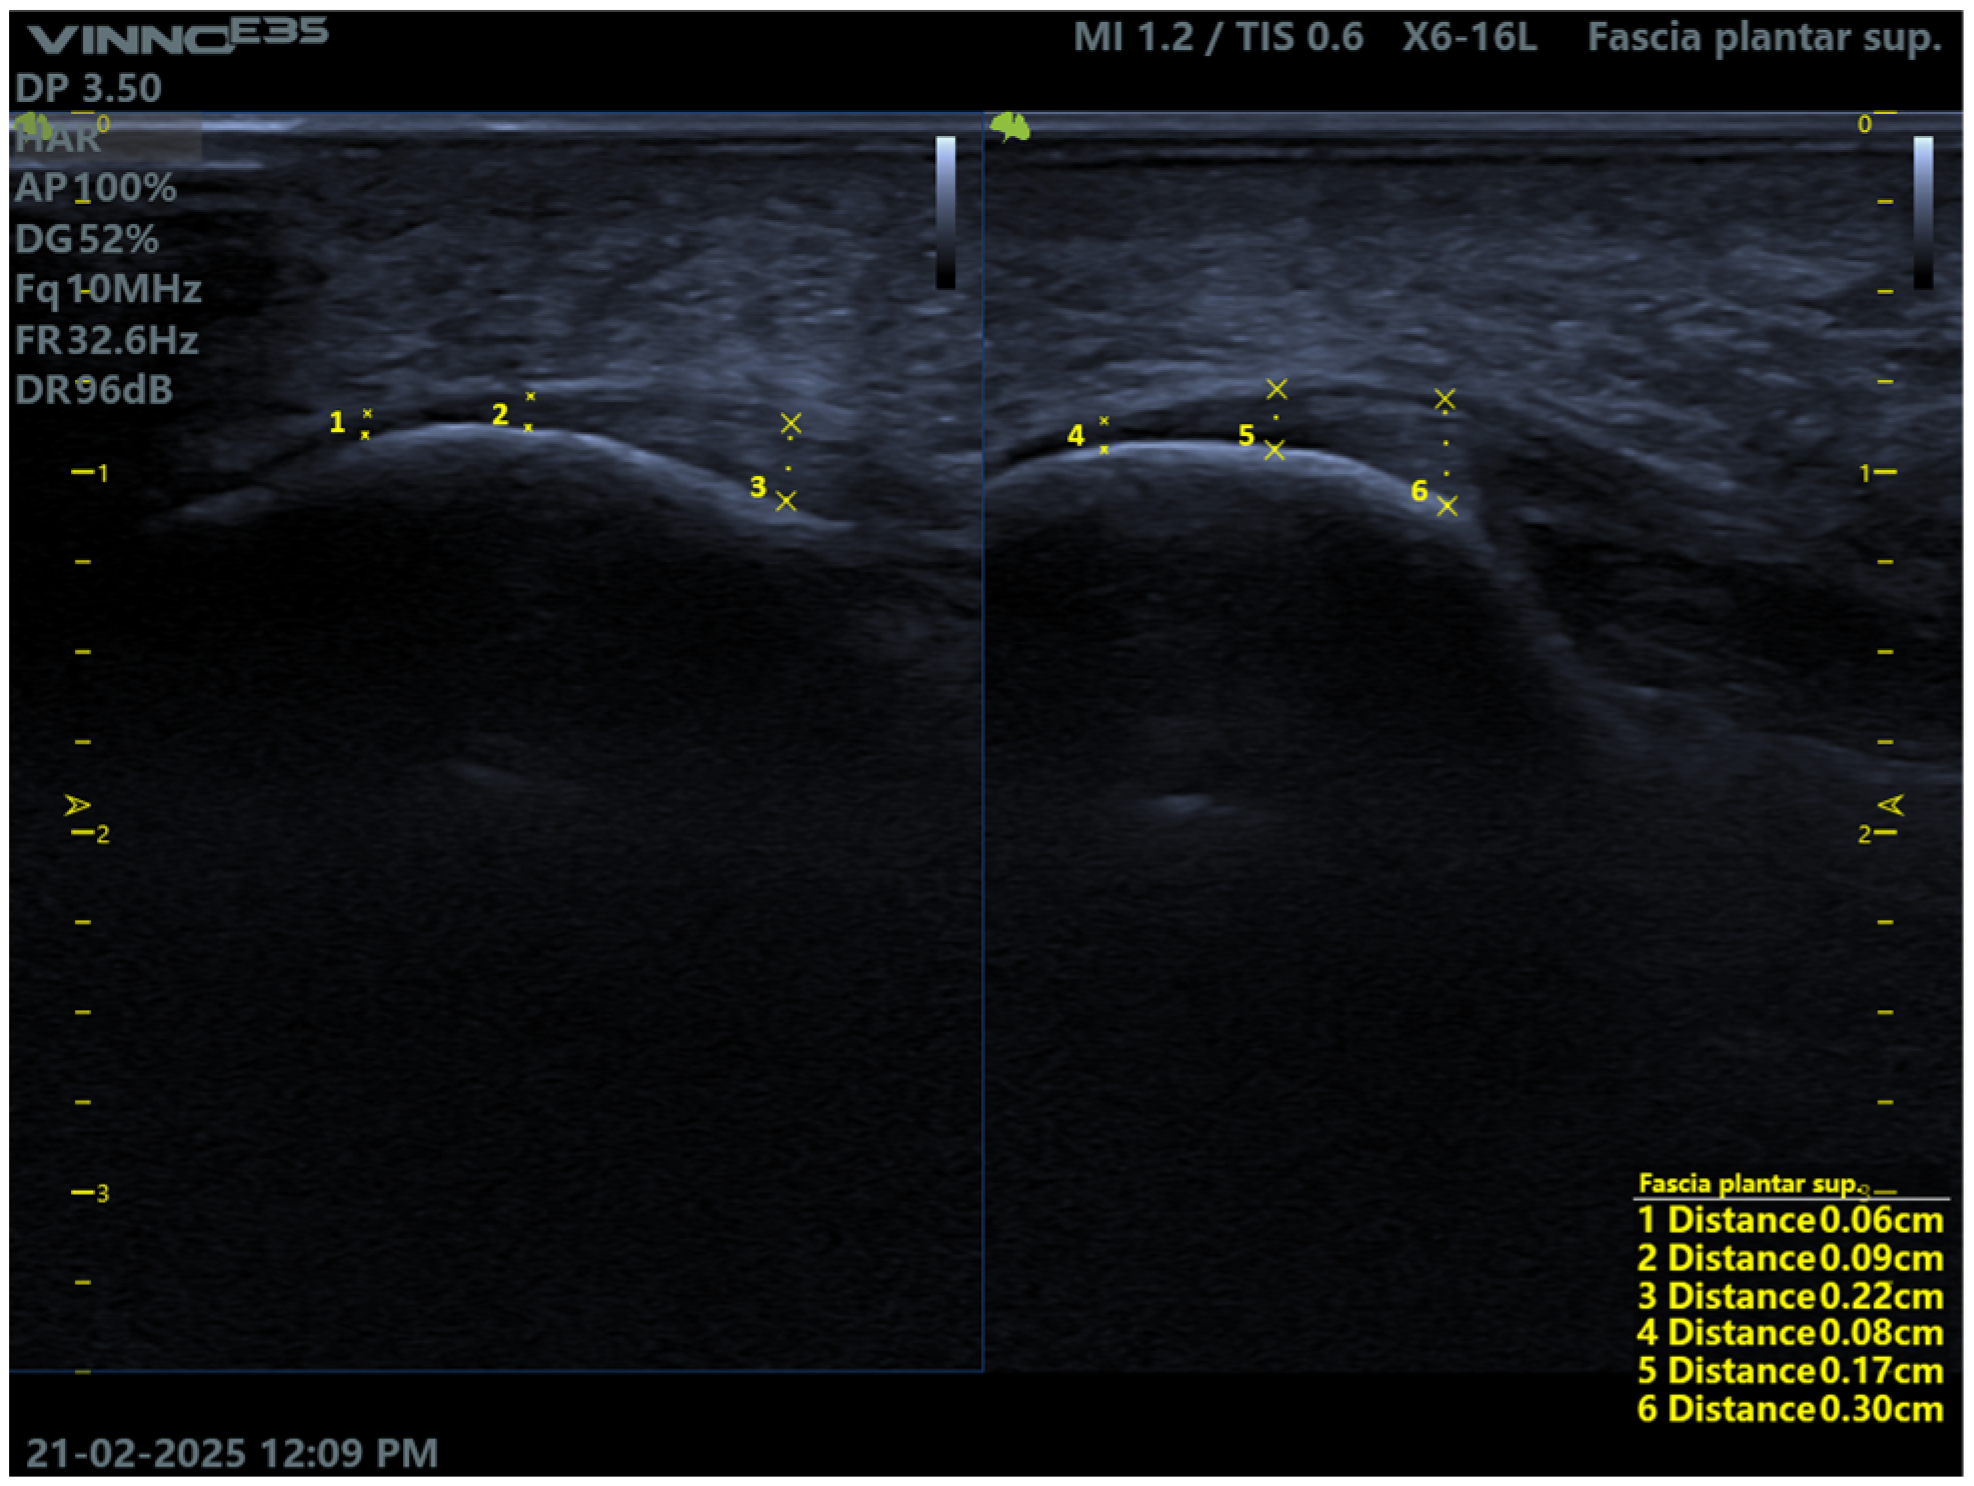

The transducer is then positioned longitudinally relative to the foot, and a precise ultrasound scan is performed to locate the insertion point of the plantar fascia. Once clearly visualized, the image is frozen on the ultrasound system to allow for accurate measurements. Using the “distance” measurement tool available in the software, three measurements are taken per foot: one at the exact insertion point of the fascia, a second at the mid-body of the fascia, and a third at a more distal location.

After all measurements are recorded and properly stored within the ultrasound software, the corresponding images are saved to ensure that all data are available for subsequent analysis and comparison (Figure 3).

Figure 3. Comparison of plantar fascia measurements in the right and left foot by the novice technician.